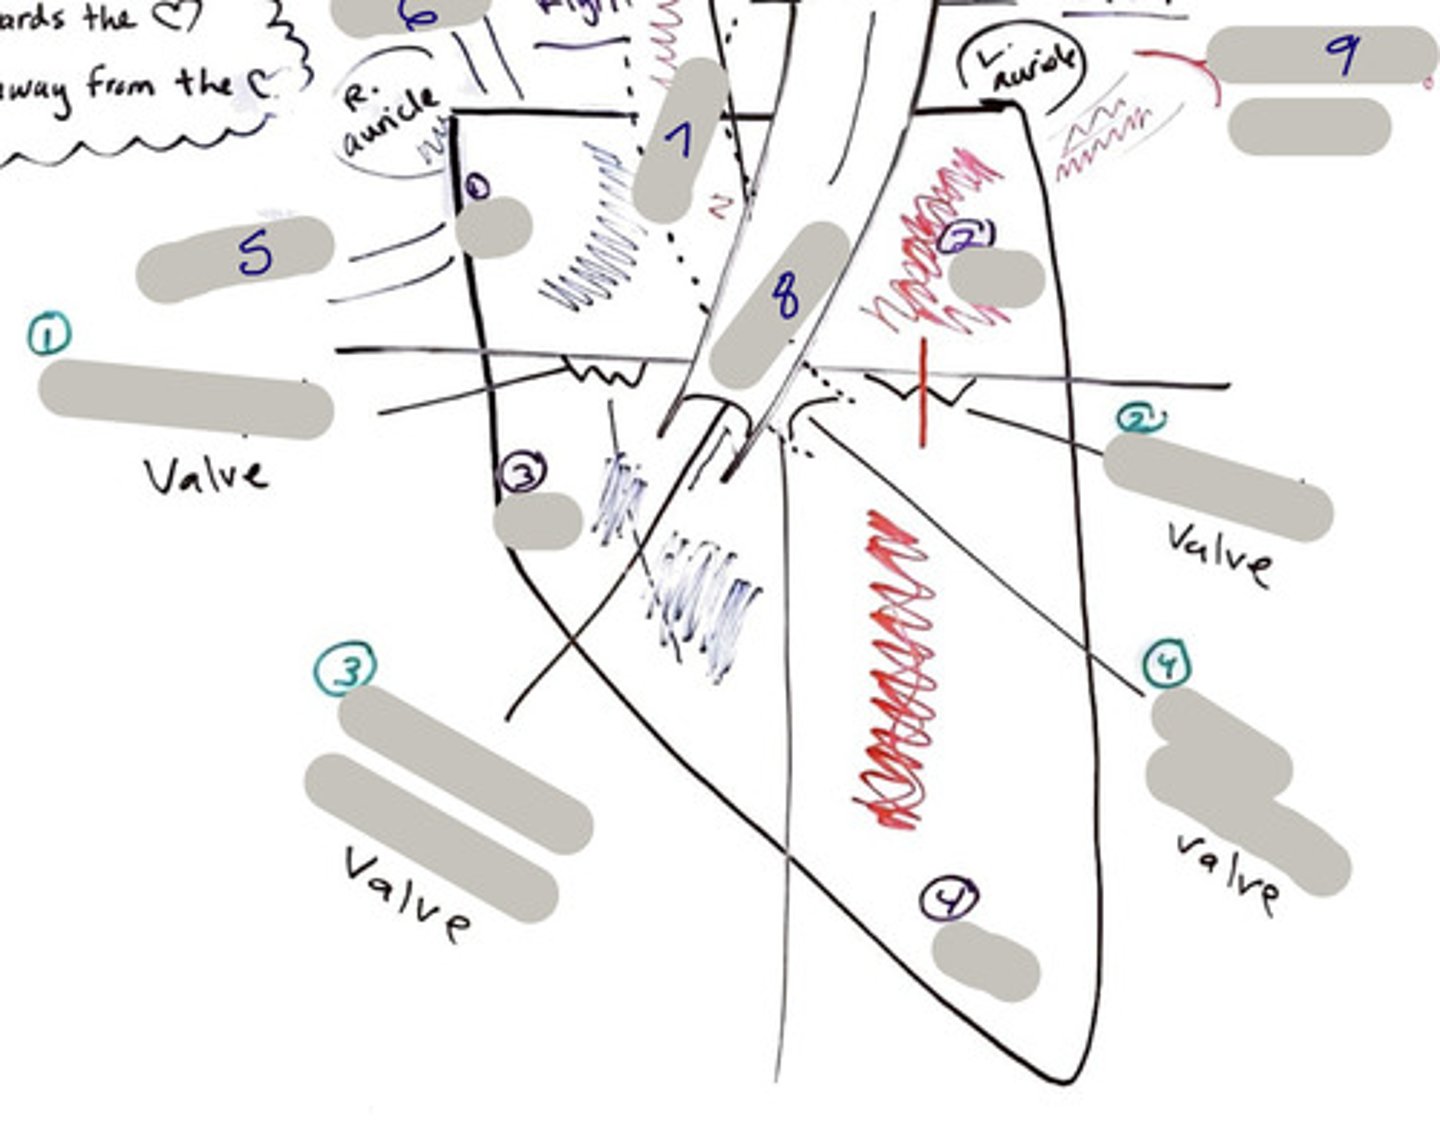

Tricuspid Valve (Right Atrioventricular Valve)

1-valve

Bicuspid valve (Left Atrioventricular Valve)

2-valve

Pulmonary Semilunar Valve

3-valve

Aortic Semilunar Valve

4-valve

Right Atrium

1-chamber

Left Atrium

2-chamber

Right Ventricle

3-chamber

Left Ventricle

4-chamber

Inferior Vena Cava

5-A vein that is the largest vein in the human body and returns blood to the right atrium of the heart from bodily parts below the diaphragm.

Superior Vena Cava

6-A vein that is the second largest vein in the human body and returns blood to the right atrium of the heart from the upper half of the body.

Aorta

7-The large arterial trunk that carries blood from the heart to be distributed by branch arteries through the body.

Pulmonary Trunk

8-carries blood from right ventricle to pulmonary arteries

Pulmonary veins

9-a vein carrying oxygenated blood from the lungs to the left atrium of the heart.